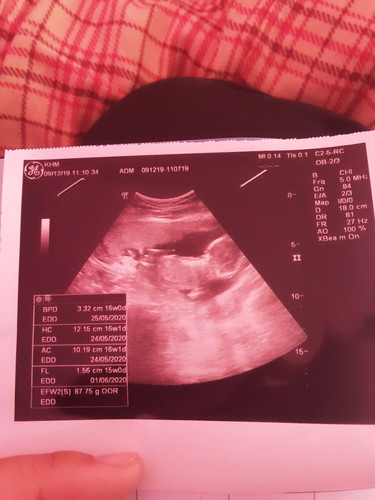

ตอนนั้นฝากท้องครั้งแรก16วีค หมอก็ซาวให้บอกหมอตัวน้องใหญ่แข็งแรงเห็นเป็นตัวเรย?? แต่ตอนนี้33+1วีค แล้วใกล้แล้วน่ะเจ้าตัวน้อยของแม่???????